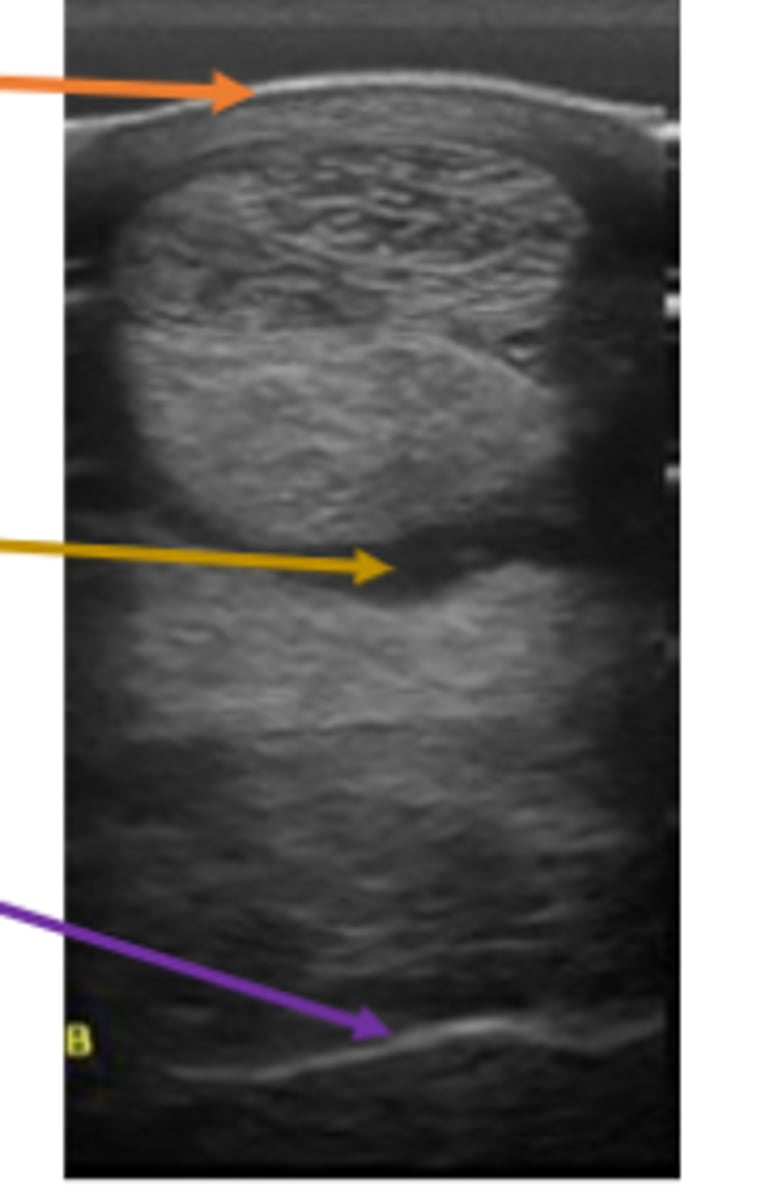

What is seen in #1 with least Acoustic Impedance?

Fluid (blood)

Solid (Stone)

Fibrous Tissue (Diaphragm)

Soft Tissue (liver)

What is seen in #2 regarding Acoustic Impedance with less penetration?

What is seen in #3 regarding Acoustic Impedance with even less penetration?

What is seen in #4 with highest Acoustic Impedance?

Black = no waves back

White = all waves back

Gray = some waves back